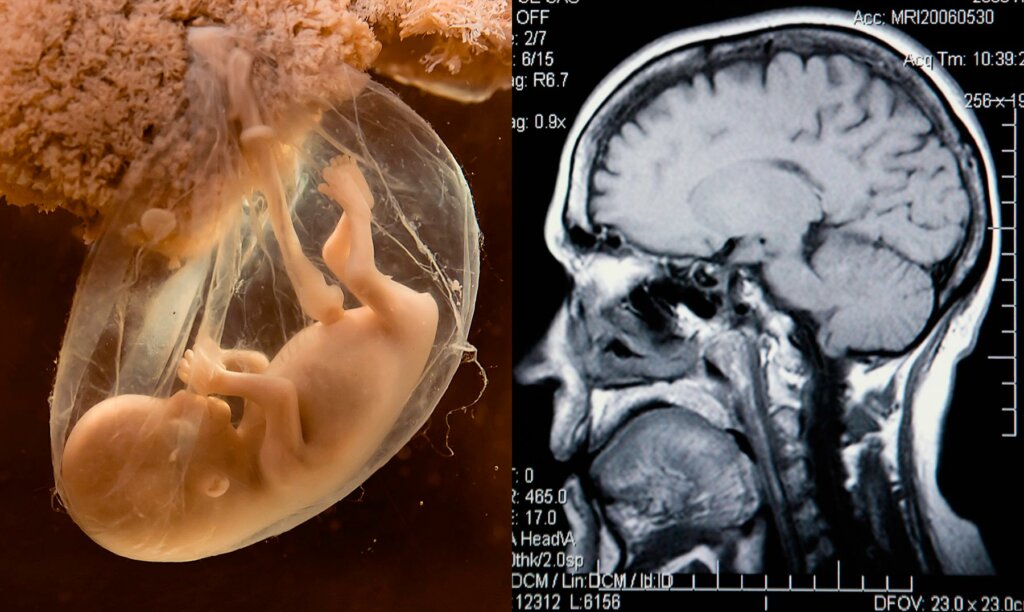

Postpartum depression has gained visibility in recent years, destroying the myth that the period after pregnancy was always a happy time. That said, depression may also develop before a woman becomes pregnant or during the pregnancy. In fact, the term perinatal depression includes depression during pregnancy and within a year after delivery.

Peripartum or perinatal depression affects approximately one in eight women. These two terms tend to be used interchangeably. However, the former term relates more specifically to women. The disorder often persists throughout the peripartum period. In fact, up to 47 percent of women with postpartum depression have experienced an antenatal episode.

Perinatal depression is associated with a spectrum of negative long-term obstetric outcomes in offspring. These include potential adverse impacts on the mother-infant relationship. It also substantially affects the well-being and functioning of women and can even lead to suicide. In moderate to severe cases, or after failure to respond to first-line psychotherapy, pharmacotherapy with antidepressants is often required. Pooled results from 40 cohort studies indicate that selective serotonin reuptake inhibitors (SSRIs) are the most widely used antidepressants.